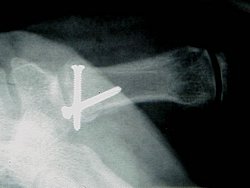

"Posilam muj prvni prispevek do sekce trauma. Suma sumarum: 2,5 hodky operace v plne narkoze, 2 sroubky v ruce, 5 stehu, 6x rentgen, 3 lahve kapacky a 3 sacky antibiotika do zily, 4 dni v nemocnici, 5 tydnu sadra... :-(

Diky vsem za sms prani. Ctibor"

Pro silné povahy přidávám detailní obrázky zranění: